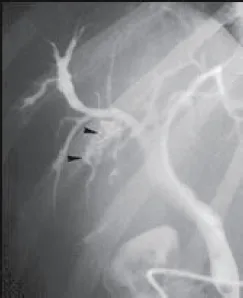

Dans à peu près 5 % des cas, le syndrome LPAC est responsable d’une dilatation sacculaire des voies biliaires intra-hépatiques qui moulent des macro-calculs cholestéroliques sans sténose biliaire sous-jacente (Fig. 5) [8]. Le diagnostic différentiel à évoquer est la dilatation primitive congénitale des voies biliaires intra hépatiques (maladie de Caroli diffuse ou dilatation primitive localisée à un lobe ou un segment).

Dans la forme particulière de syndrome LPAC avec dilatation des voies biliaires intra-hépatiques autour de macro-calculs, le recours à la résection du segment ou du lobe atteint peut se justifier si le patient présente des angiocholites récidivantes malgré le traitement par AUDC.